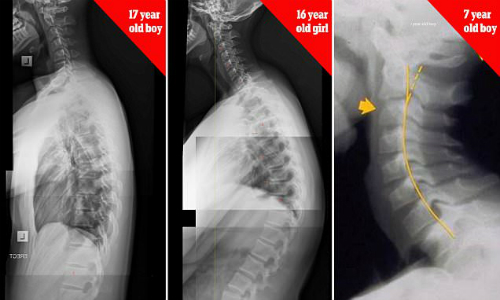

Xương sống của bé trai 17 tuổi, bé gái 16 tuổi và bé trai 7 tuổi bị biến dạng do nghiện thiết bị điện tử. Ảnh: James Carter.

Nhiều phụ huynh khi thấy con em dùng điện thoại chỉ quan tâm liệu trẻ có xem các nội dung không phù hợp mà không nhắc nhở về tư thế ngồi. Chuyên gia trị liệu cột sống là tiến sĩ James Carter (Australia) cảnh báo trẻ em 7 tuổi có thể bị gù lưng, cong vẹo cột sống do sử dụng smartphone và tablet quá nhiều. Hội chứng được gọi là "chiếc cổ nhắn tin" đang gia tăng một cách đáng báo động.